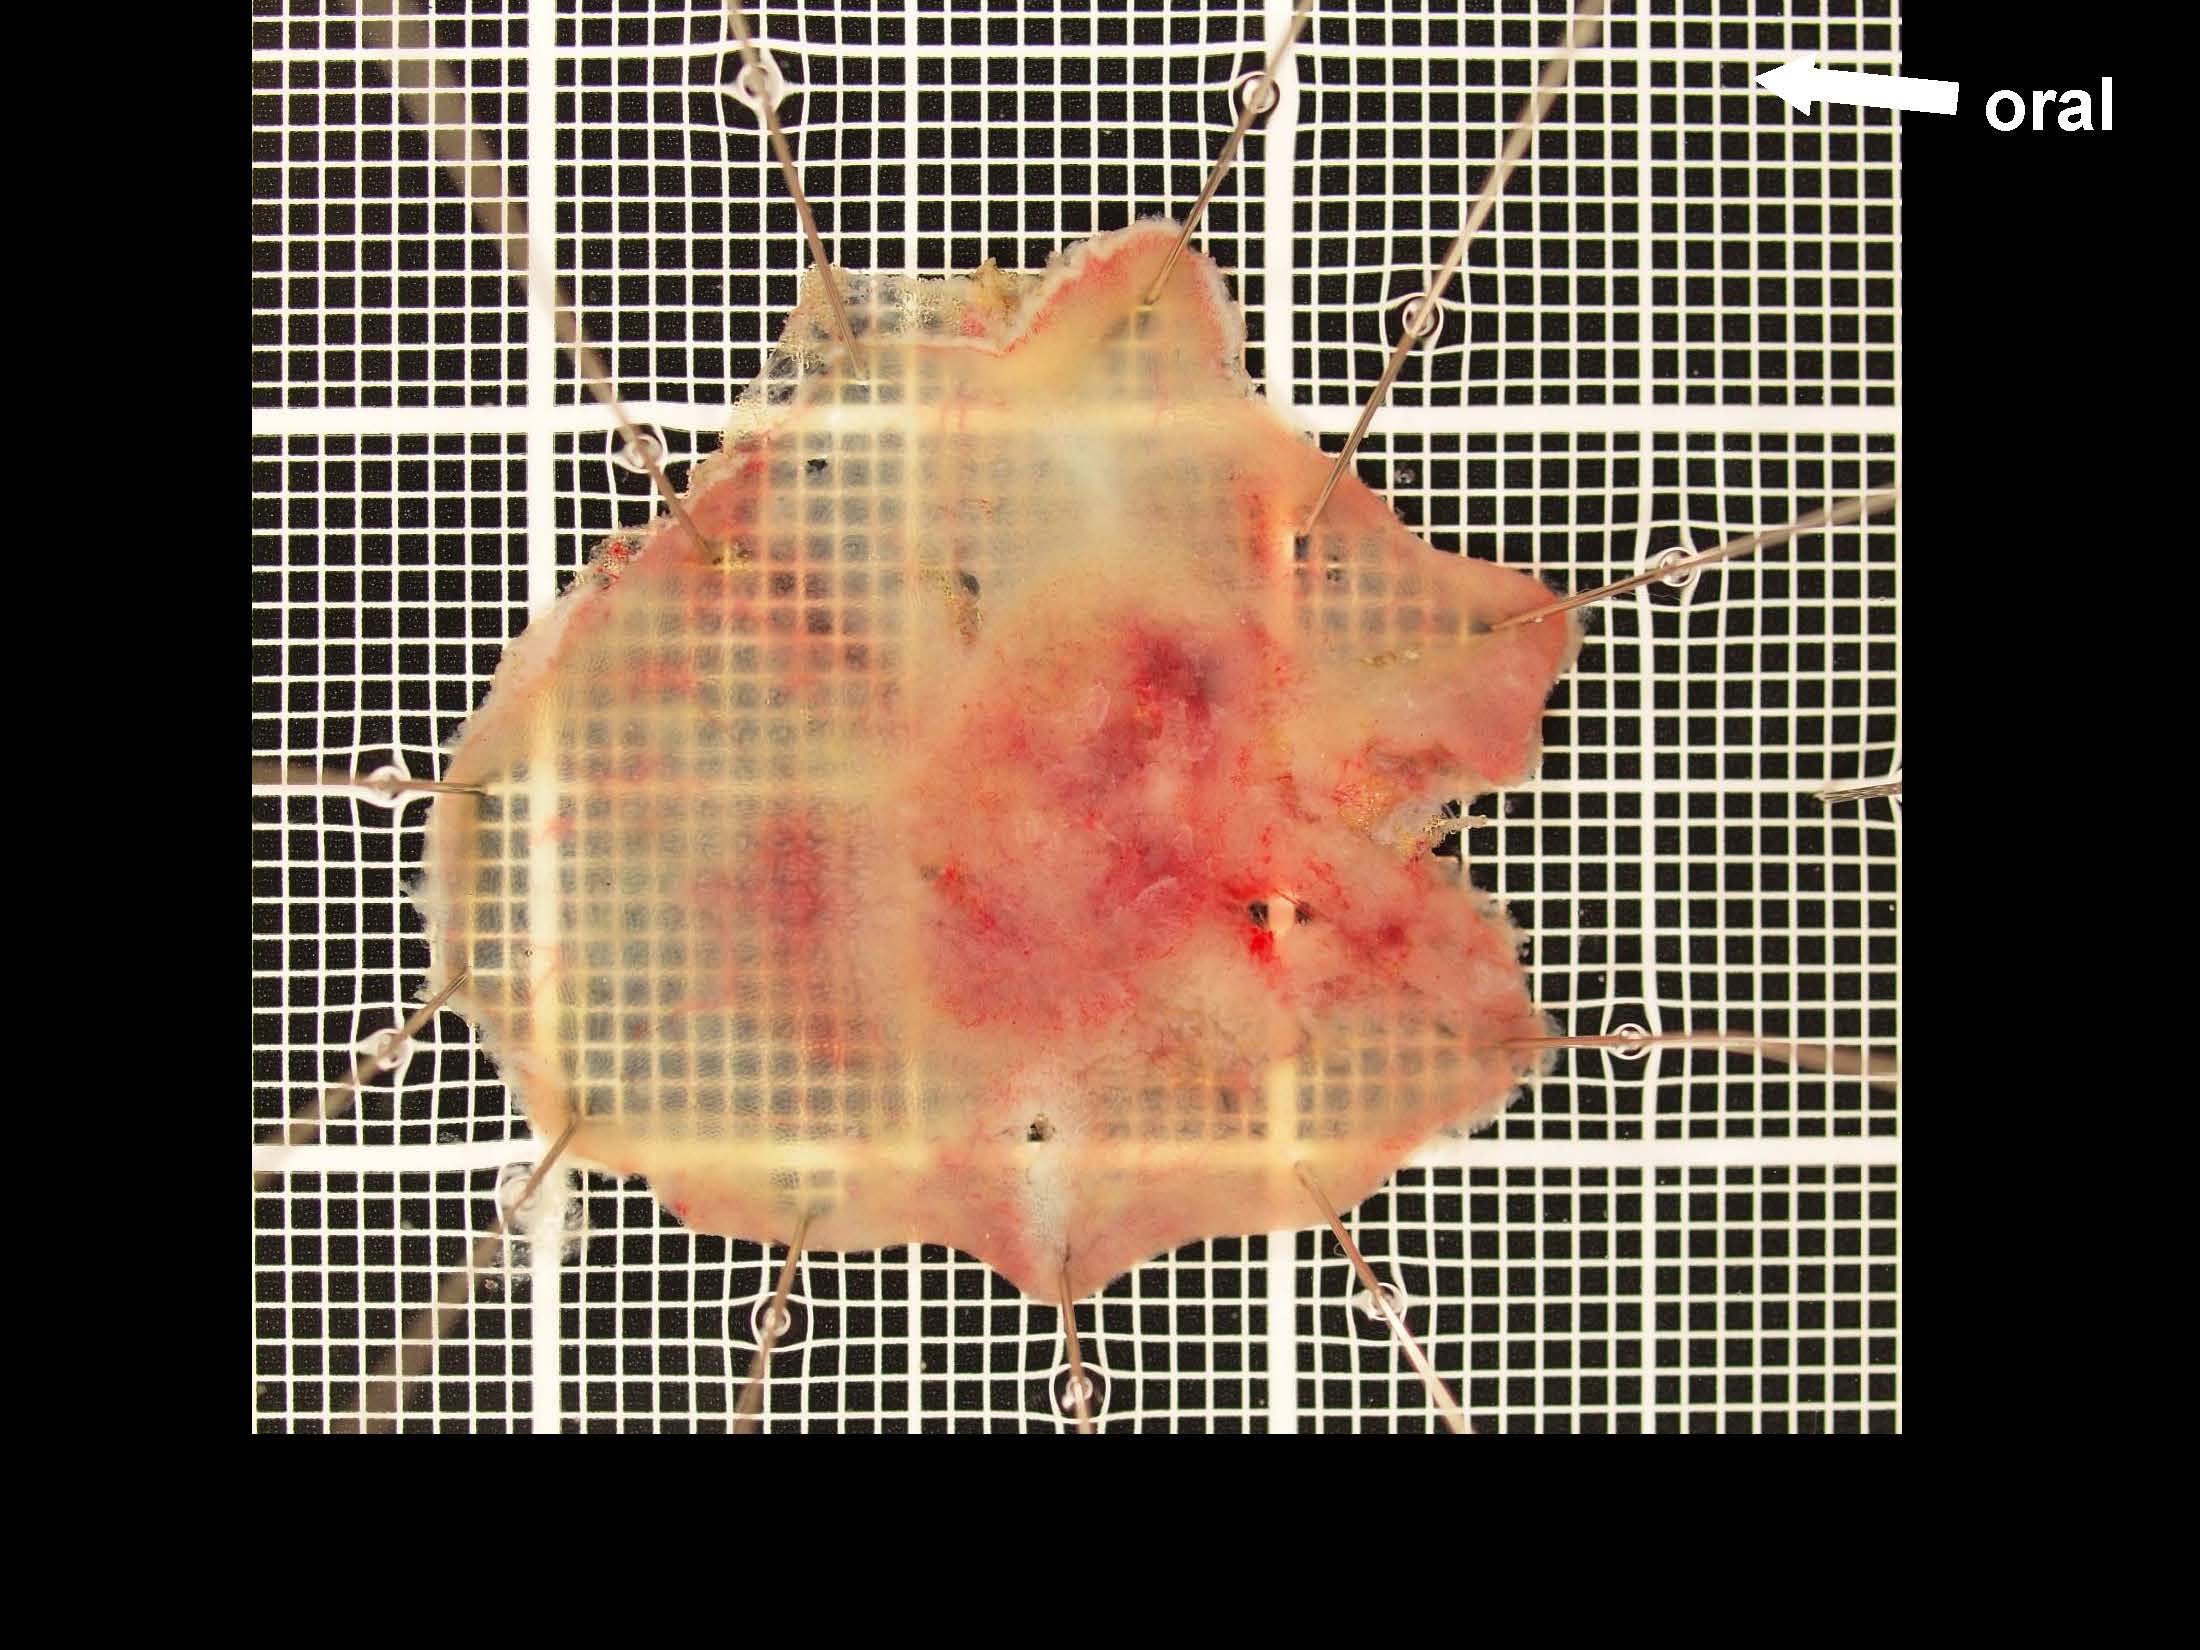

消化管Mapping~大腸~ 2021.10.27

消化管Mapping~大腸~

消化器内科

内視鏡検査・治療

消化管Mapping